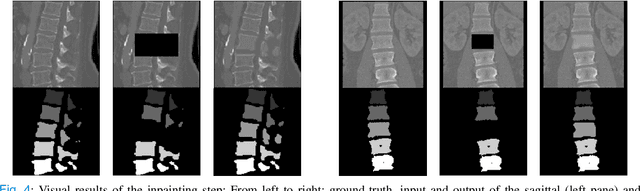

Abstract:Symptomatic spinal vertebral compression fractures (VCFs) often require osteoplasty treatment. A cement-like material is injected into the bone to stabilize the fracture, restore the vertebral body height and alleviate pain. Leakage is a common complication and may occur due to too much cement being injected. In this work, we propose an automated patient-specific framework that can allow physicians to calculate an upper bound of cement for the injection and estimate the optimal outcome of osteoplasty. The framework uses the patient CT scan and the fractured vertebra label to build a virtual healthy spine using a high-level approach. Firstly, the fractured spine is segmented with a three-step Convolution Neural Network (CNN) architecture. Next, a per-vertebra rigid registration to a healthy spine atlas restores its curvature. Finally, a GAN-based inpainting approach replaces the fractured vertebra with an estimation of its original shape. Based on this outcome, we then estimate the maximum amount of bone cement for injection. We evaluate our framework by comparing the virtual vertebrae volumes of ten patients to their healthy equivalent and report an average error of 3.88$\pm$7.63\%. The presented pipeline offers a first approach to a personalized automatic high-level framework for planning osteoplasty procedures.